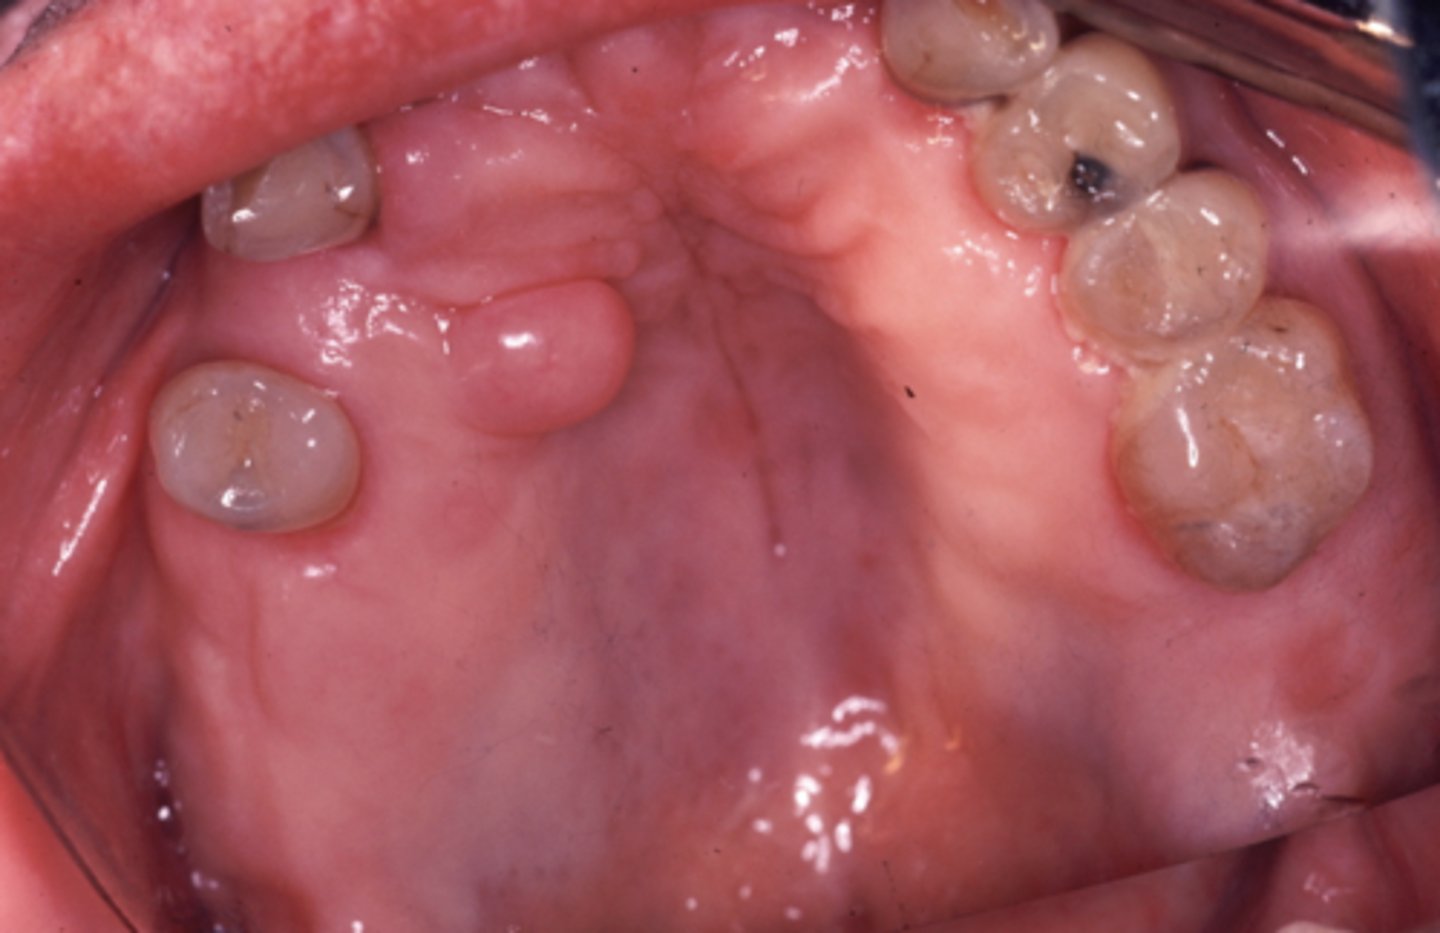

what is congenital epulis of the newborn?

proliferation of granular cells that appears as a soft, round, exophytic mass attached to the alveolar mucosa

congenital epulis is more common on the (maxilla/mandible)

maxilla